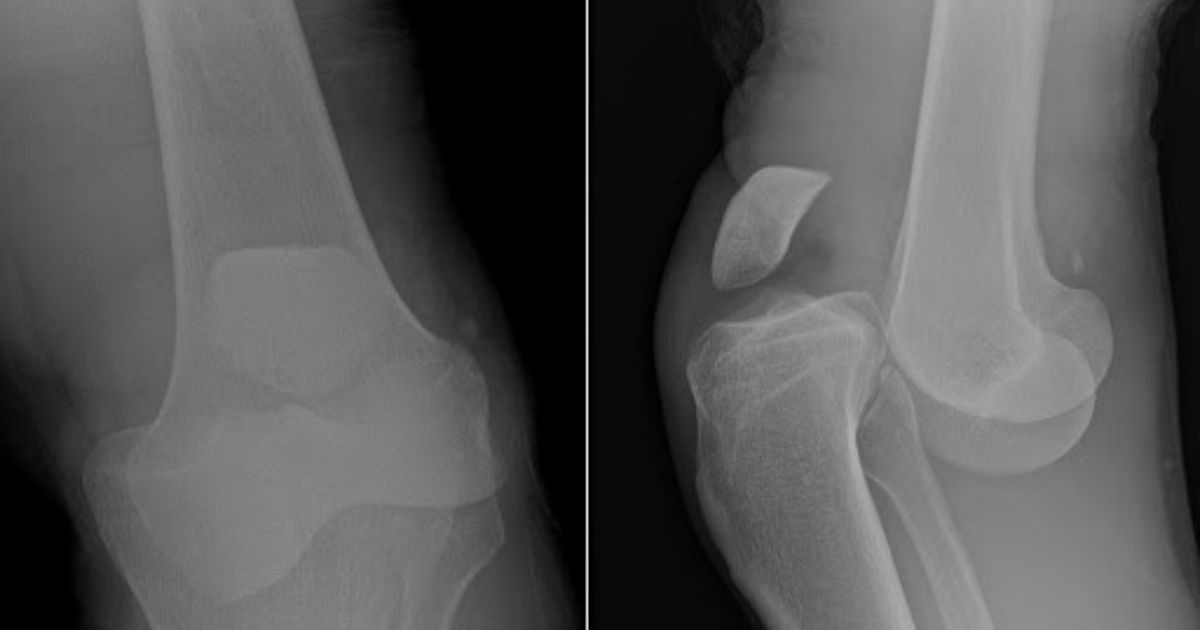

Gãy xương vùng gối

Khi có cú va chạm mạnh trong lúc thi đấu, đầu gối có thể bị gãy xương bánh chè hoặc xương chày. Đây là chấn thương nghiêm trọng, đòi hỏi can thiệp y tế ngay lập tức.